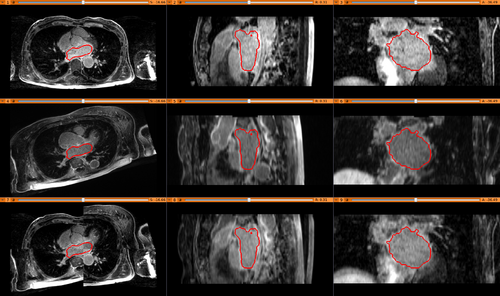

- GUI of module and one result

Results. Top row: Pre-op LGE-MRI with its segmentation of the left atrium (LA). Middle row: Pre-op LA contour overlayed on the registered Post-op LGE-MRI. See the matching of the LA region. Bottom row: checker-board view of Pre-op and registered Post-op LGE-MRIs: they match well at the LA region but badly otherwise, indicating the necessity of using segmentation to aid the registration.